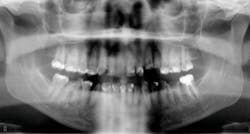

DURING the last few years, some of the greatest innovations in implant designs have occurred in relation to the immediate placement of implants. “Old-school” implant designs generally involved cylindrical, nontapered implant bodies with relatively dull and shallow threads. But modern, more recent implant designs have included tapered implant bodies with sharper, deeper, and more aggressive threads. This has allowed for more engagement in the bone (osseocompatibility), with greater primary stability, which has equated to earlier loading times. These more modern designs have also created greater success rates, which has led to the immediate implant procedure being more popular with general practitioners in the United States.

Another reason immediate placement is advantageous is that once the extraction is complete, the hole is usually already in the proper place for the implant. You may have to redirect your osteotomy slightly palatally, mesially, or distally, but the socket serves as an excellent guide for placement. In some cases, especially premolars, you can use an implant with aggressive threads to place without any osteotomy at all. You can engage the mesial and distal walls to achieve primary stability. This greatly shortens the appointment time, lowers risk, and increases patient satisfaction. Figures 1 and 2 show a MorsTorq in site No. 21 that was placed after an atraumatic extraction during my most recent two-day Louisiana Implant Institute course. Note the sharp threading on the MorsTorq, which allows for optimized immediate placement performance.There are some circumstances where immediate placement is not desirable. If the socket is too large to engage the mesial and distal walls and vital anatomical structures are located just apical to the socket, immediate placement is not recommended. Chronically infected sites also present a higher risk for immediate placement. If you can completely rid the socket of all soft tissue and the patient has the appropriate antibiotics onboard, it is possible. However, most of these cases are more predictably treated with early placement (waiting four to six weeks without grafting) or delayed placement (three to six months with grafting).